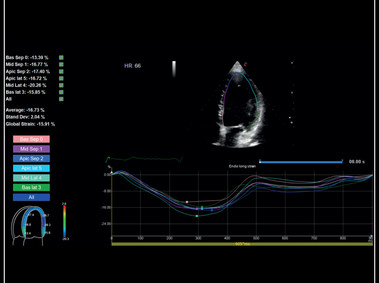

Đánh giá vận động vùng tâm thất trái toàn diện với Siêu âm đánh dấu mô cơ tim X-strain